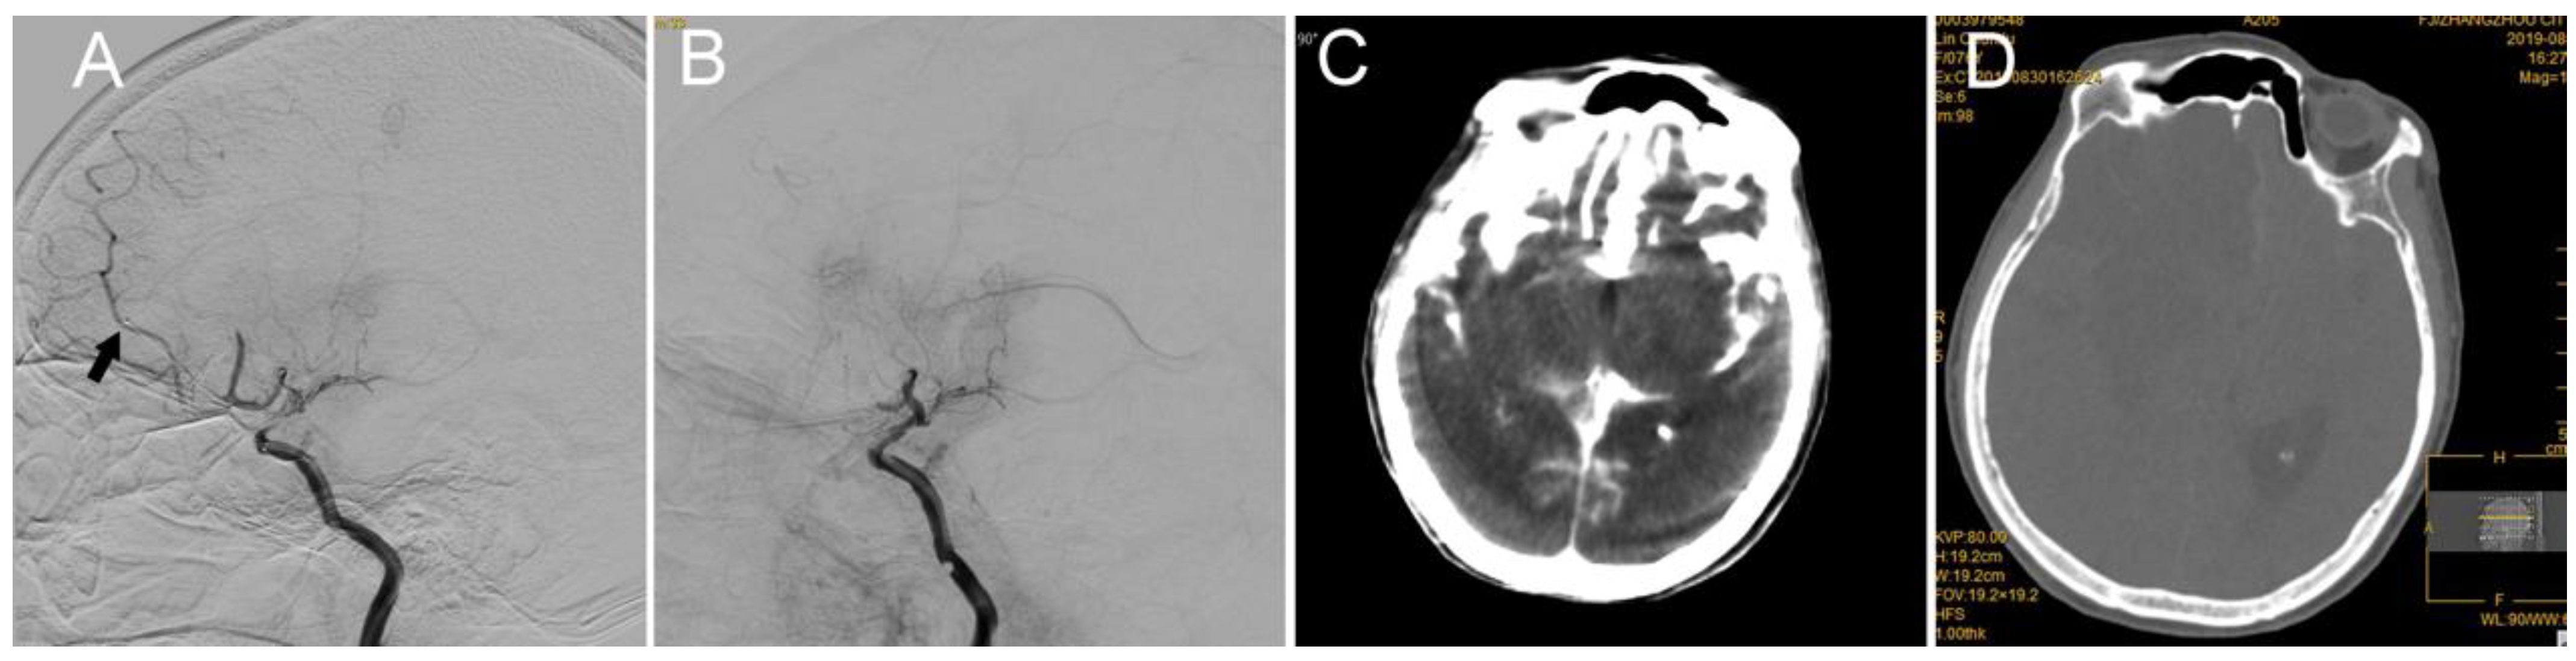

5. Case 4: Anterior Cerebral Artery (ACA) A2 Segment

| 4 | R-M1D ICAS | IV heparin | No | Stent retriever | Solitaire 4 × 20 1 pass | R M1D | Resistance withdrawing stent retriever | IA thrombin | No new hemorrhage | mTICI 2b, mRS 3 at 3 months |